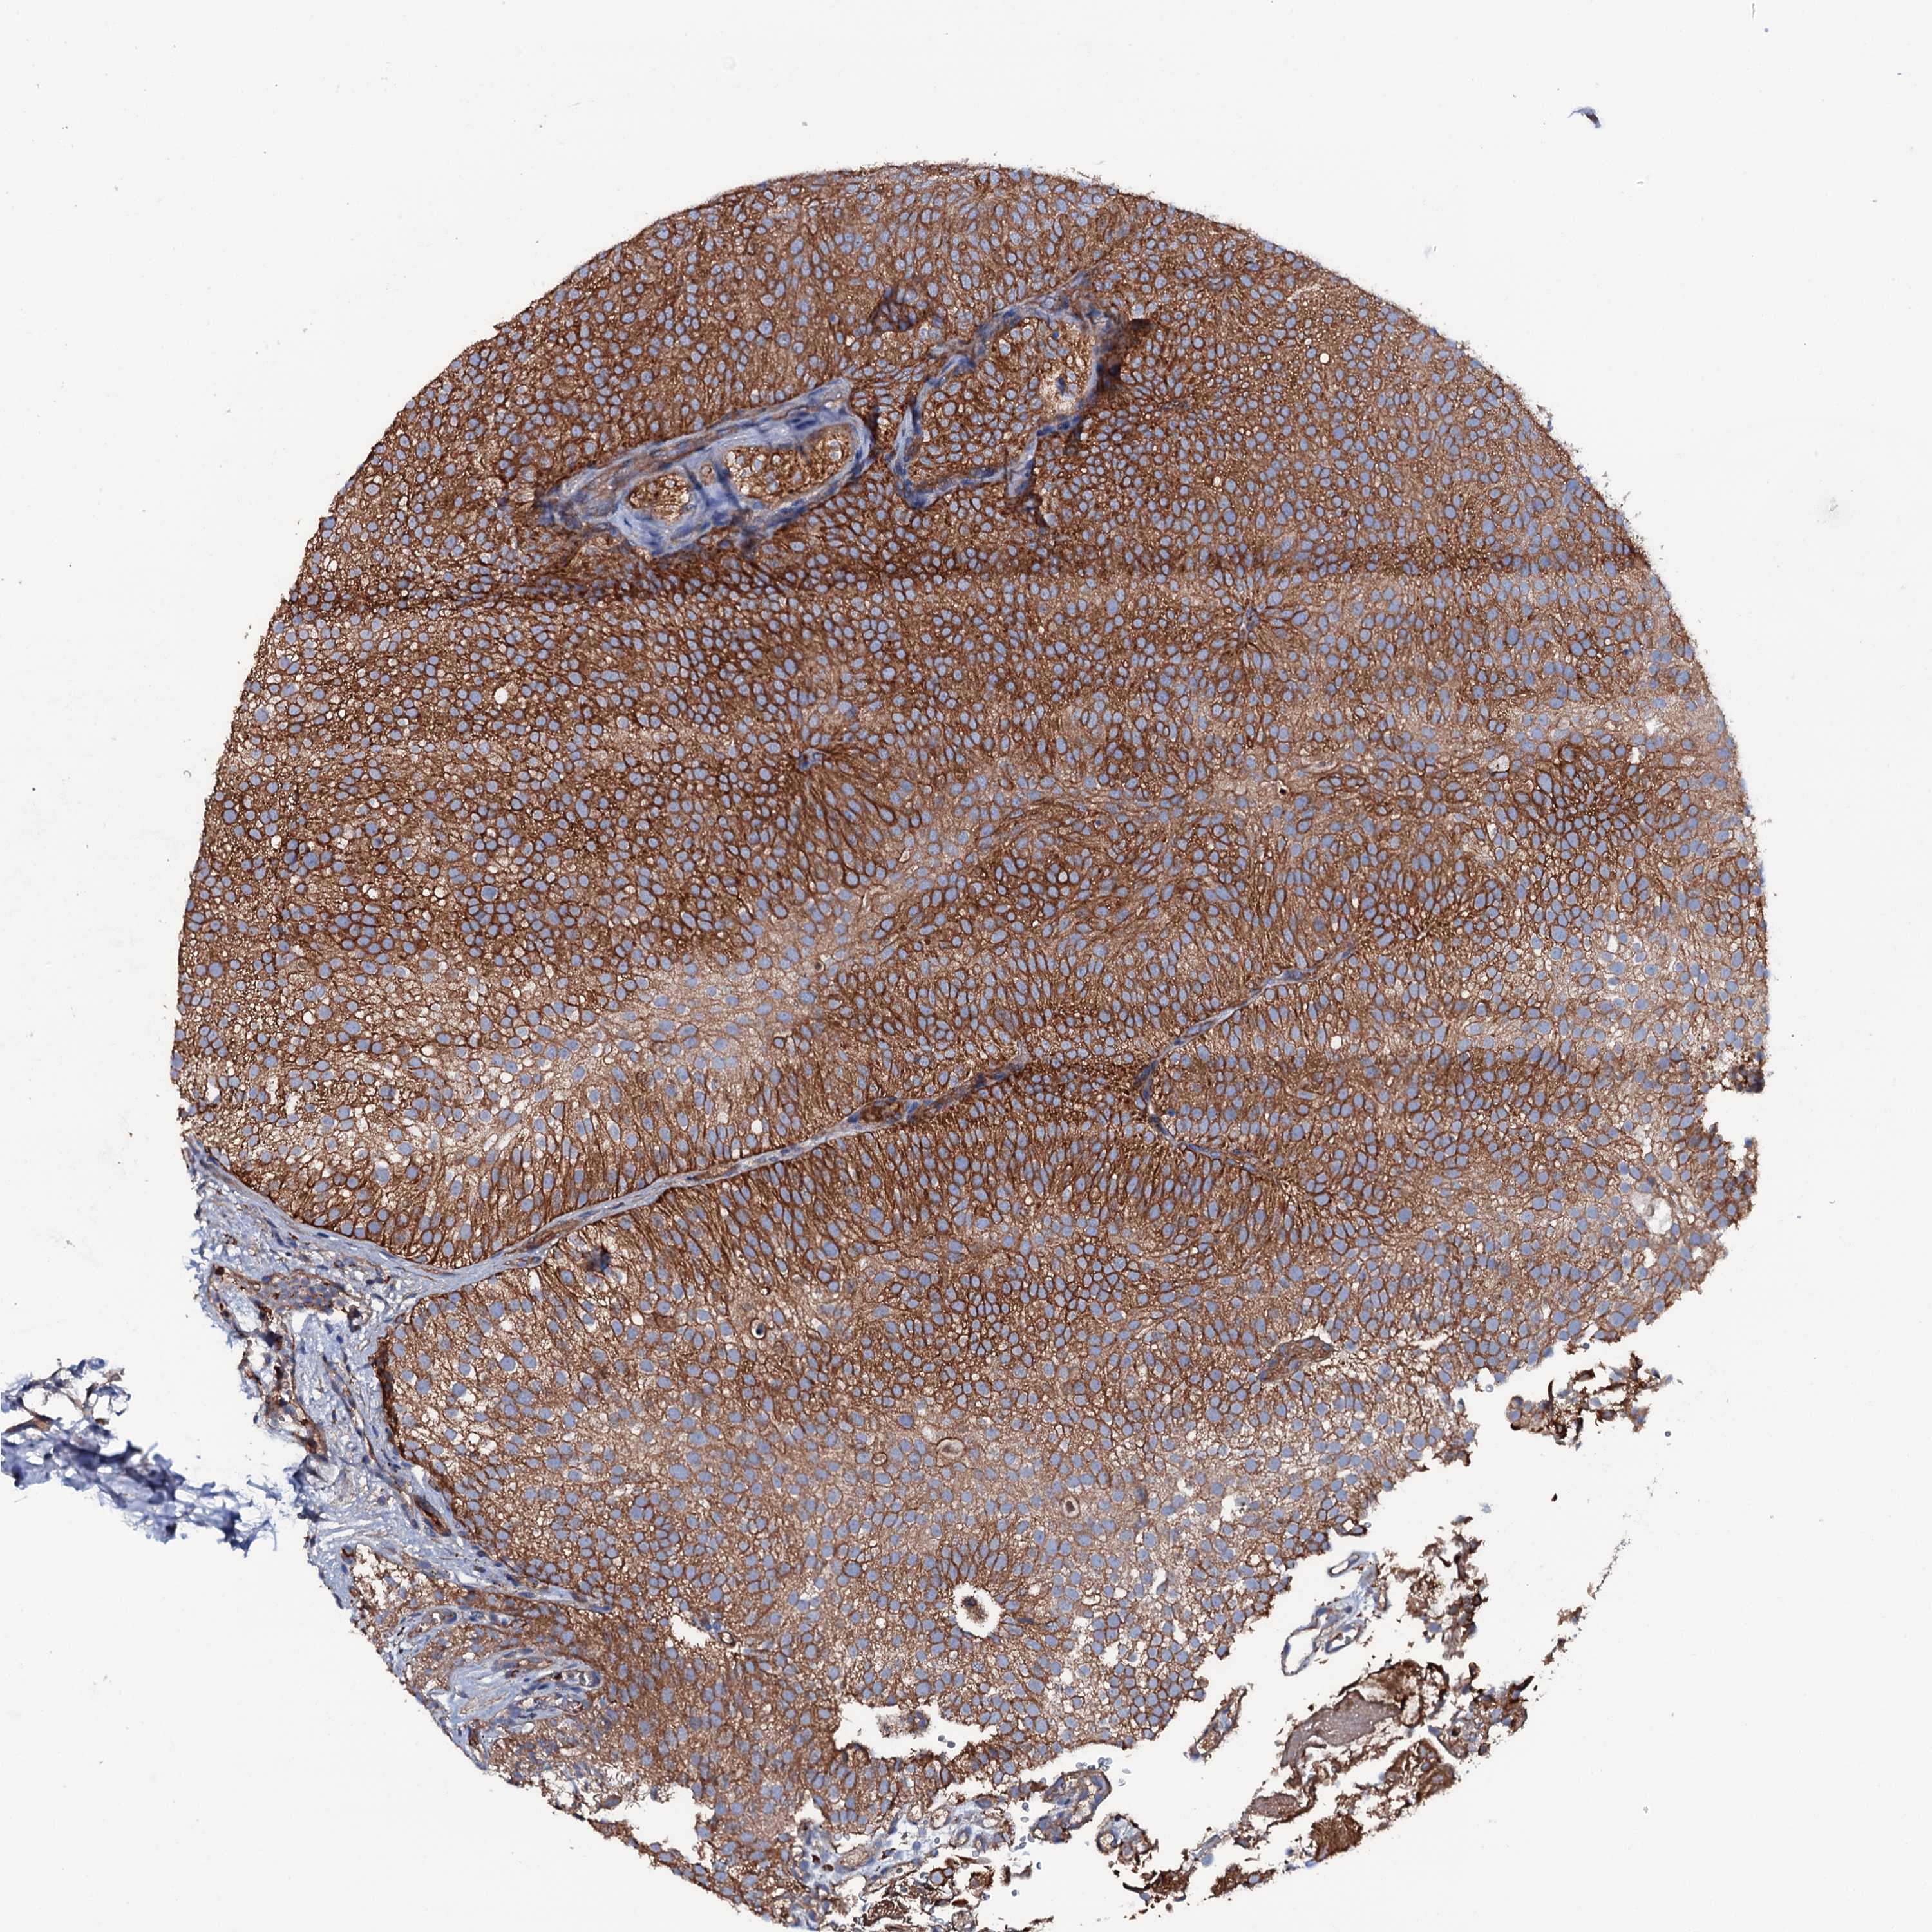

UROTHELIAL CANCER - Protein expressioni

A mouse-over function shows sample information and annotation data. Click on an image to view it in a full screen mode. Samples can be filtered based on level of antibody staining by selecting one or several of the following categories: high, medium, low and not detected. The assay and annotation is described here.

Antibody stainingi

Antibody staining in the annotated cell types in the current human tissue is reported as not detected, low, medium, or high, based on conventional immunohistochemistry profiling in selected tissues. This score is based on the combination of the staining intensity and fraction of stained cells.

Each image is clickable and will lead to virtual microscopy that enables deeper exploration of all samples and also displays staining intensity scores, fraction scores and subcellular localization as well as patient and tissue information for each sample.

Antibody HPA020873

Antibody HPA040413

Staining

High

Medium

Low

Not detected

Intensity

Strong

Moderate

Weak

Negative

Quantity

>75%

75%-25%

<25%

None

Location

Nuclear

Cytoplasmic/membranous

Cytoplasmic/membranous,nuclear

Urothelial carcinoma, High grade

Urothelial carcinoma, Low grade

Urothelial carcinoma, NOS